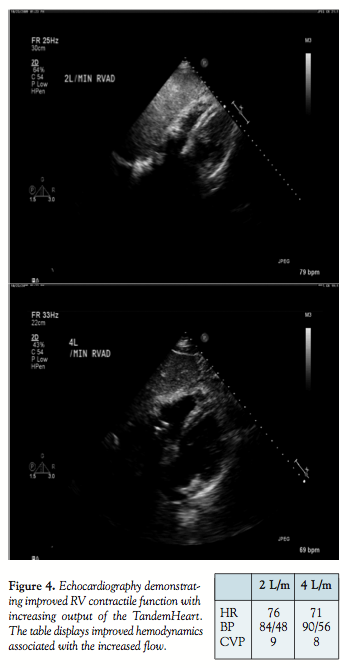

The patient was maintained on the RVAD and the IABP for bi-ventricular support and anticoagulated with heparin. Within 24 hours of RVAD placement the patient’s hemodynamics improved with reduction in heart rate from 87 bpm to 77 bpm, reduction in central venous pressure from 14 mmHg to 7 mmHg, and increase in blood pressure from 87/57 mmHg to 117/68 mmHg. Vasoactive agents were weaned two days after RVAD placement and the patient was successfully extubated. Given this clinical improvement and the ongoing risk of bleeding and infection with prolonged insertion, the RVAD cannulae and IABP were removed at bedside on day three with sustained hemodynamic stability. The patient was transferred to stepdown floor and subsequently discharged home on hospital day 7. Serial echocardiograms to evaluate his cardiac function one year after this event noted an ejection fraction of 61% with normal right ventricular performance.